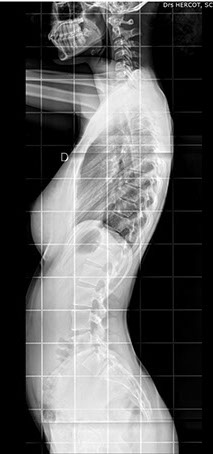

Elle peut être réalisée sur tout le corps et permet avant tout l’étude des os,

Pour les os et articulations : des fractures, de l’arthrose, des malformations

Elle utilise les rayons X, consistant à impressionner un film qui sera plus ou moins noirci selon l’organe radiographié : ainsi les os apparaîtront blancs et l’air noir ; les tissus mous seront de différentes nuances de gris.

Dans notre cabinet, la technique est numérisée et la surface sensible est en fait un capteur et non un film, ce qui permet de modifier le contraste après avoir pris le cliché et d’agrandir certaines zones pour mieux voir.